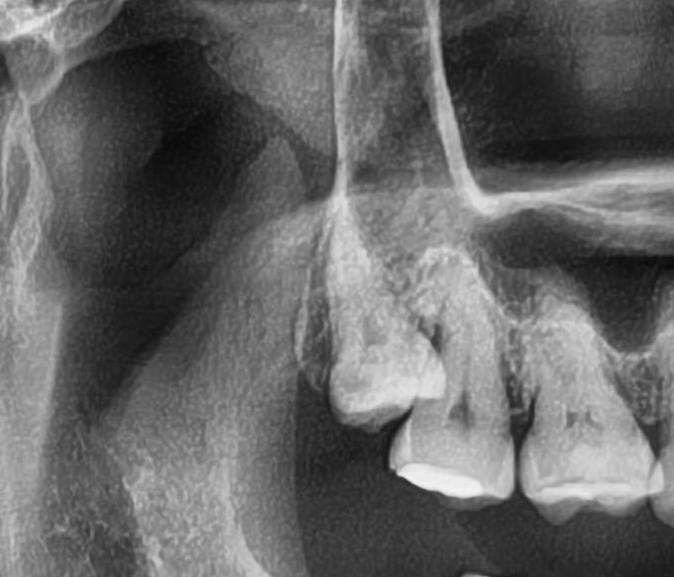

まず1人目の患者様。

年明けに予定していた右下の親知らずの抜歯を行いました。

左下の親知らずは一部が見えており、レントゲンで詳しく確認すると、手前の歯を押すように斜めに生えていました。

無事に抜歯終了!